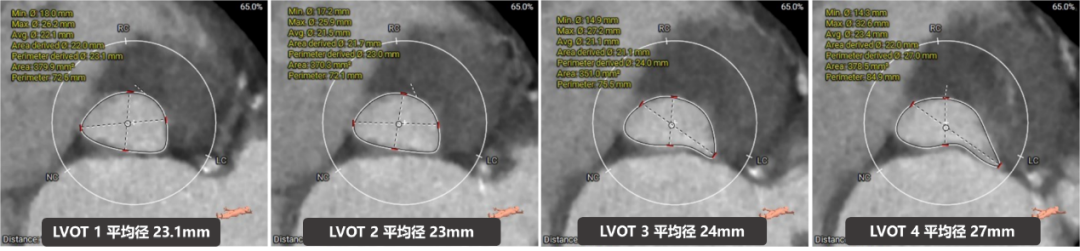

流出道结构测量

收缩期流出道结构

收缩期流出道可提供6mm筒状区域。

舒张期流出道结构

舒张期流出道约3mm筒状区域;

流出道收缩期和舒张期可锚定区域波动较大,整体约4mm辅助锚定区域。